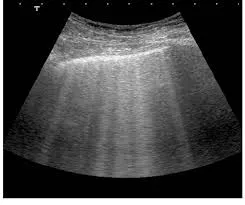

Na prática devemos solicitar um TC abdome (sem contraste) ou RM abdome par avaliar as características do rim e suas dimensões. O paciente deve ter entre 18 e 10 anos e ser classificado como típico, isto é, os cistos renais distribuídos de forma difusa e bilateral.

Observação: pacientes que apresentam cistos renais distribuídos de forma unilateral, segmentada ou os cistos são bilaterais, mas com atrofia renal associado, serão classificados como atípicos (2A ou 2B), nestes casos não é necessário calcular a volumetria renal.